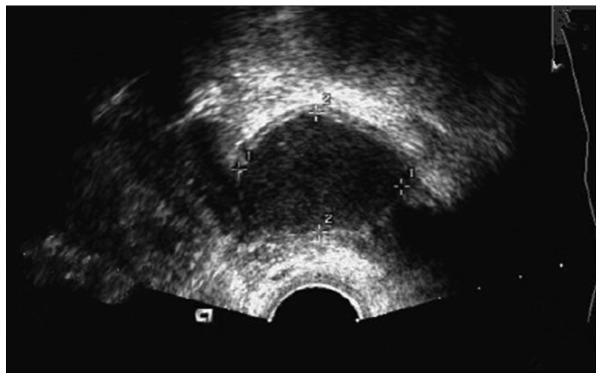

This study evaluates the curative effects laparo-scopic hysterectomies performed to treat uterine fibroids and determined the impact of the procedures on ovarian blood supply. A total of 124 patients with uterine fibroids admitted and treated in our hospital from December 2014 to December 2015 participated in the study. Two groups of 62 patients each were formed according to different operating plans; one group of patients underwent abdominal (open) panhysterectomy and were set as the control group; with the other group of patients were treated with laparoscopic hysterectomy and were set as the observation group. Ovarian endocrine function tests and blood supply changes were measured in both groups before the operation and one month after it, and the clinical conditions of all the patients were followed up for 24 months after surgery. Our results showed the duration of operation, amount of bleeding and time to recovery after the procedure were significantly lower in the patients in the observation group (P<0.05). Also, compared with preoperative conditions, the levels of PRL, FSH, E2, LH and other ovarian function markers in both groups were significantly lower one month after the operation, but the levels of the patients in the observation group were still significantly higher than those of the patients in the control group (P<0.05). Likewise, the surgeries affected the ovarian blood supply in patients of both groups, as evidenced by the lower levels of PI, RI, Vmin, Vmax and other blood supply indexes observed by Doppler ultrasound a month after the operations. However, the impact of the surgery on the ovarian blood supply was less marked in the patients in the observation group as their levels remained higher than those of patients in the control group (P<0.05). The numbers of patients with completely healed abdominal muscular layers in the observation group were always significantly higher than those of patients in the control group, at every different time point examined (1, 4, 8 and 12 months after surgery) (P<0.01). At the end of the 24 months of the follow-up period, the recurrence rate of fibroids for patients in the observation group was 4.8%. In our hands, the laparoscopic hysterectomy procedure to treat uterine fibroids showed the usual advantages over the abdominal open hysterectomy, like small trauma, short surgical procedure and rapid postoperative recovery, but it also proved to cause a significantly smaller impact on ovarian blood supply and should be considered whenever uterus preservation is a priority.

本研究评估了腹腔镜子宫切除术治疗子宫肌瘤的疗效,并确定了该手术对卵巢血液供应的影响。2014年12月至2015年12月在我院收治并接受治疗的124例子宫肌瘤患者参与了本研究。根据不同的手术方案将患者分为两组,每组62例;一组患者接受腹式(开放式)全子宫切除术,设为对照组;另一组患者接受腹腔镜子宫切除术,设为观察组。在两组患者手术前及术后1个月测量卵巢内分泌功能指标及血液供应变化,并对所有患者术后进行24个月的临床随访。结果显示,观察组患者的手术时间、出血量及术后恢复时间均显著低于对照组(P<0.05)。此外,与术前相比,两组患者术后1个月PRL、FSH、E2、LH等卵巢功能指标水平均显著降低,但观察组患者的这些指标水平仍显著高于对照组(P<0.05)。同样,手术均影响了两组患者的卵巢血液供应,术后1个月通过多普勒超声观察到PI、RI、Vmin、Vmax等血液供应指标水平降低。然而,手术对观察组患者卵巢血液供应的影响较小,因为其指标水平仍高于对照组(P<0.05)。在术后不同时间点(术后1、4、8和12个月)检查时,观察组腹部肌肉层完全愈合的患者数量始终显著高于对照组(P<0.01)。随访24个月结束时,观察组患者子宫肌瘤的复发率为4.8%。在我们的研究中,腹腔镜子宫切除术治疗子宫肌瘤比腹式开放式子宫切除术具有创伤小、手术时间短、术后恢复快等常见优势,但也证明对卵巢血液供应的影响明显较小,在以保留子宫为优先考虑时应予以考虑。